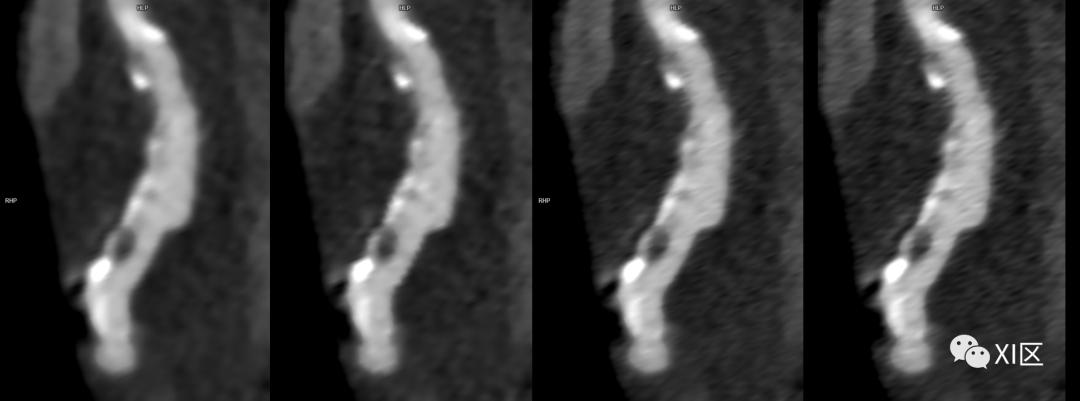

SOMATOM Force CT常规重建0.75 mm图像(左)、0.6 mm(192x0.6 mm)图像(左中)与IVR重建0.6 mm(288x0.6 mm)图像(右中)、0.6 mm(576x0.6 mm)图像(右)比较。使用IVR技术的图像冠脉内钙化斑块及非钙化斑块显示更清晰。

SOMATOM Definition Flash光子CT常规重建0.6 mm(128x0.6 mm)图像(左)与IVR重建0.6 mm(384x0.6 mm)图像(右)比较。使用IVR技术的图像关节面更平滑,骨小梁及骨折细节显示更清晰。

SOMATOM Force CT常规重建0.6 mm(192x0.6 mm)图像(左)与IVR重建0.6 mm(288x0.6 mm)图像(中)0.6 mm(576x0.6 mm)比较(上排:全局视图;下排:局部放大显示)。使用IVR技术的图像关节面更平滑,骨小梁及骨折细节显示更清晰。